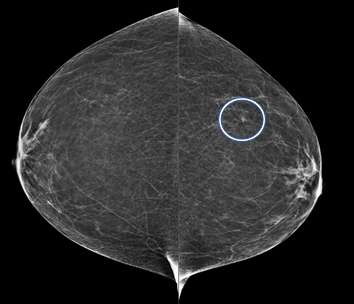

Global Asymmetry:

A global asymmetry is a finding seen on two projections of significantlyincreased breast tissue occupying greater than one quadrant. Global asymmetries that have been evaluated without suspicious features are most lynormal variantsand do not require additional follow up.

Implant displaced MLO and CC views of the breast demonstrate increased density through the left breast, consistent with a global asymmetry.